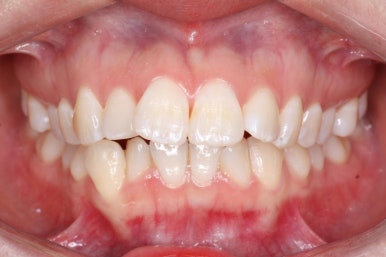

다시 이번 환자분으로 돌아가, 입 안모습을 보시겠습니다.

부산무턱교정 키다리아저씨치과에서 처음 내원하셨을 당시의 입 안의 모습입니다.

아래턱이 작아서 상대적으로 윗니들이 많이 돌출되었고, 뻐드러져 있습니다. 윗니들이 배열되어 있는 형태도 V자에 가깝게 입천장이 좁은 양상입니다.